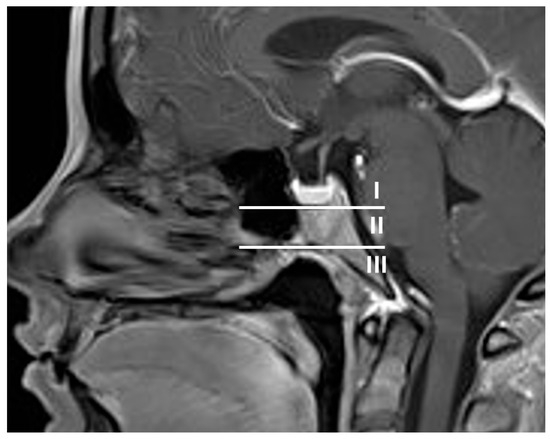

Preoperative and postoperative magnetic resonance and computerized tomography imaging were reviewed to assess tumor extension, specifically the type of clivus infiltration (focal or diffuse growth into the clivus, state of the cortical lamella), extent of resection, residual tumor and visibility of the pituitary gland. The type of sellar destruction was classified as diffuse only if almost the entirety of the sella floor was destroyed, while multifocal perforation of the sellar floor with consecutive spread into the cancellous clivus was classified as focal. In order to assess the extent of clival infiltration, three regions of tumor growth along the clivus were defined (Figure 2 and Figure 3): along the dorsum sellae from the posterior clinoid processes to the floor of the sella (region I), from the sellar floor to the floor of the sphenoid sinus (region II) and inferior to the floor of the sphenoid sinus (region III). Furthermore, the preoperative CT imaging was specifically reviewed for the type of clival infiltration (diffuse erosion and infiltration versus predominantly cancellous infiltration with intact cortical lamella of the sellar floor, Figure 4). Surgical notes (intactness of diaphragm, identification of pituitary gland and intraoperative cerebrospinal fluid leak) and all available follow-up data at last follow-up were reviewed as well. If a case was operated on between 2015 and 2025 due to a recurrence, the initial surgery was analyzed if data were available; otherwise, the recurrent case was analyzed. Thus, in two cases, an earlier operation was considered which was performed using a microsurgical transsphenoidal approach.

Figure 2. To assess surgical accessibility and facilitate surgical planning, the clivus was separated into three regions: region I: posterior clinoid to the floor of the bony sella, behind the pituitary; region II: from the sellar floor to the floor of the sphenoid sinus—there is a straight trajectory from the anterior wall of the sphenoid to this region; region III: inferior to the floor of the sphenoid sinus—this lower region proves particularly difficult to access surgically if only the sphenoid sinus is opened.